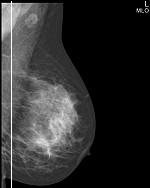

Шаг 3. Формат приемника рентгеновского изображения

В маммографии существует два общепринятых формата приемника рентгеновского изображения: 18х24 см и 24х30 см. На приемнике 18х24 см одномоментно (за одну экспозиции, без дополнительной укладки) можно исследовать грудь приблизительно до 2 размера включительно, а на приемнике 24х30 см - до 5 размера включительно.

Маммографы, рассчитанные на работу с приемников 18х24 см, стоят дешевле своих аналогов 24х30 см, однако маммографы с приемником 24х30 см являются более универсальными в своем применении.

Следует отметить, что исследование молочной железы большего размера, чем формат приемника, осуществляется в несколько экспозиций, что приводит к увеличению лучевой нагрузки на пациента, повышению общего времени обследования, повышению дискомфорта пациента, вызванного многократной компрессией органа, кроме этого, усложняется анализ серии рентгенограмм врачом рентгенологам.

Простой пример: во время скринингового обследования исследуют обе молочные железы в двух проекция (прямой и косой), если молочная железа целиком помещается на приемник, то делают четыре снимка, если молочную железу приходится снимать в два этапа, то делают уже 8 снимков.

◄ прямая проекция (кранио-каудальная) – CC (КК)

◄ косая проекция (медио-латеральная) – MLO (МЛК)

Пример сравнения классической маммограммы и томосинтезного среза

FFDM (2D) / BTM (3D)